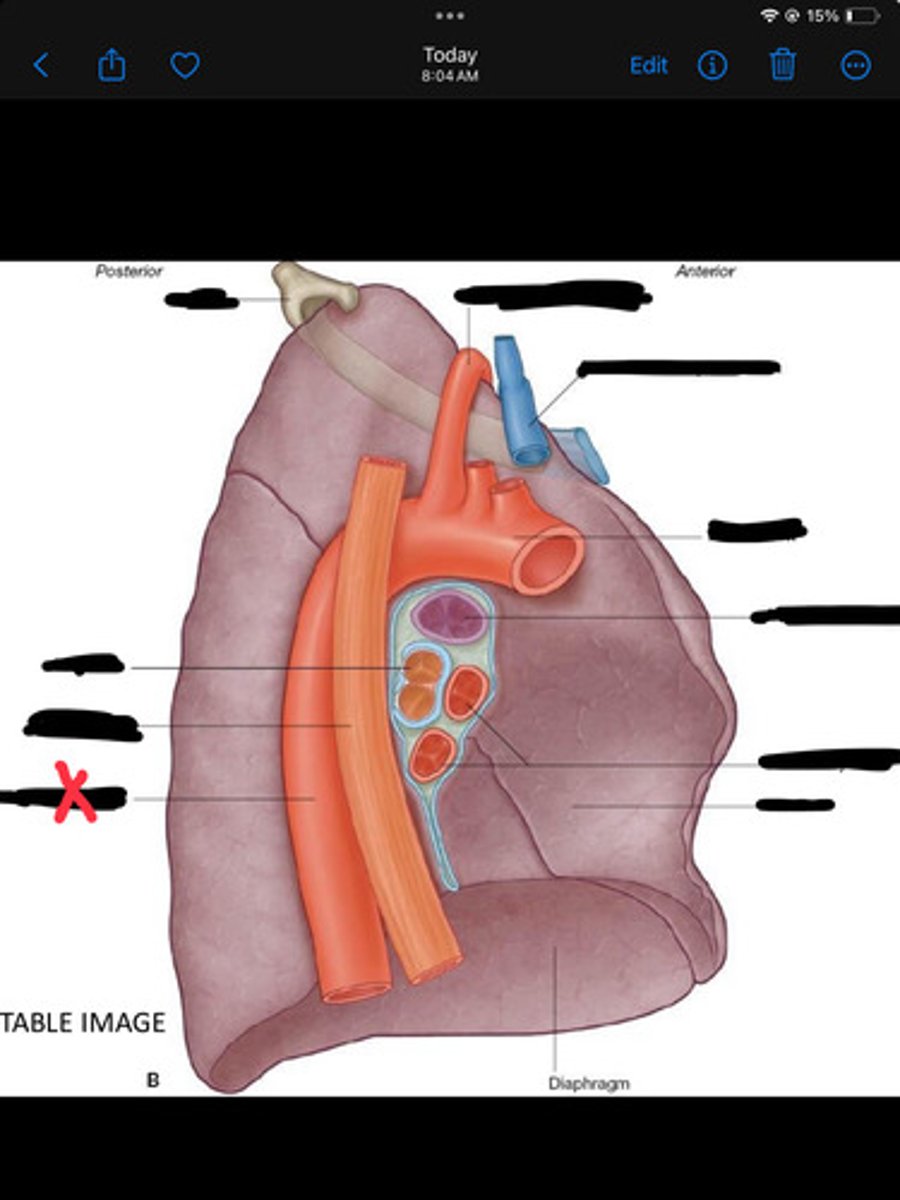

Pulmonary artery

Bronchus to superior lobe

Pulmonary veins

Diaphragm